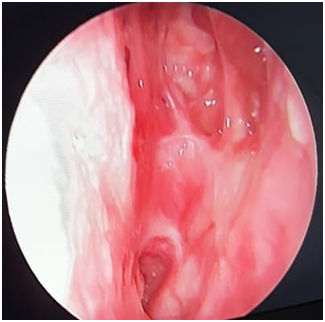

48 year old male coast guard personnel, a known case of Primary Hypertension and Type II Diabetes Mellitus, presented to this centre with Left nasal mass and bleeding from Left nostril of 04 months duration. There was history of similar complaints for the past 23 years. History of bathing in pond in his village which is in Southern part of India since his childhood. No history of rhinorrhoea /excessive sneezing/trauma to nose. Patient was diagnosed as Rhinosporidiosis and underwent excision of the mass thrice, in 1994, 2006 and 2017. On evaluation, there was a red friable mass filling Left nasal cavity, with spores seen on the surface and bleeds on touch (Figure 1). Computed Tomography of Paranasal sinuses (PNS)–shows Left nasal cavity filled with soft tissue on the anterior aspect, absent middle and inferior turbinate (Figure 2). He underwent Nasal Endoscopic Excision (Microdebrider & CO2 laser assisted)-mass was removed using Bipolar diathermy and CO2 laser, the lateral wall of the nasal cavity was drilled at basisphenoid , Agger nasi and at medial maxillary wall. CO2 Laser was used at nasal septum and nasopharynx. In our centre we are using CO2 laser especially at the areas of contact over nasal septum nasal floor & at nasopharynx. Histopathological Examination (HPE) report shows-numerous variably sized thick walled sporangia containing numerous spores, foci of ruptured sporangia also noted with spilling of spores into the adjacent stroma, with chronic inflammatory infiltrates (Figure 3). Post-operative period was uneventful; he was started on Tablet Dapsone 100 mg, 1 tab daily for 01 year.